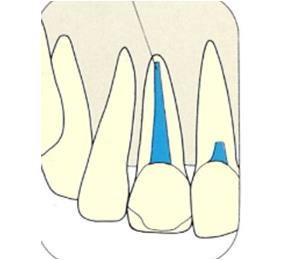

こちらのレントゲン写真を見てください。どちらかの歯医者さんで神経を取っています。根管に入れる薬は白く映ります。赤矢印部分です。一番右側が模式図ですが、青い部分が薬、根っこの先の赤点が化膿している部分です。

薬がほとんど入っていないのがわかります。黄矢印部分です。青矢印まで薬が入らないといけないのですが、全く入っていません。その結果、根っこの先が黒くなっています。膿が貯まって化膿すると黒く写ってくるのです。

別な歯科医院で治してもらいました。薬が根の先まで入っているのがわかります(黄矢印)。 根尖の黒い影が消失しています(赤矢印)。骨が再生すると白く写るようになります。

ガッタパーチャポイントは、理想的には歯根(シコン)の先ピッタリが良いと言われています。

しかし先ほど説明したように根管(コンカン)の形態は非常に複雑怪奇です。なので一概にピッタリが良いと限らないケースもあります。

ここでは一応、根尖(コンセン)付近が良いということにしておきましょう。

上の図にあるように神経の管に入れる薬が根尖(コンセン)まで入っていなかったり、途中までしか入っていなかったり、薬がスカスカだったりするとその空間にばい菌が繁殖して感染を起こします。

そうすると神経を取ったはずなのに、その後歯ぐきが腫れて痛くなるのです。

この根っこの病気を根尖性歯周炎というのです。そしてこの根尖性歯周炎を治すことを感染根管治療と言います。

大事な話なのでもう一度説明します。

①の写真はどちらかの歯医者さんで神経を取ってもらったレントゲン写真です。根っこの中に薬が全く入っていません。

②の模式図で青く描かれている部分が薬です。

根の先を見ると小豆ぐらいの大きさの黒い影が見えます。根の中でばい菌が繫殖し感染を起こすとこのような黒い影ができます。黒い影の部分は膿(ウミ)が貯まっています。こうなると腫れて痛みが出てくるのです。

③、④の写真はそれを治した後のレントゲン写真とその模式図です。白く映っている薬が根の先まできちんと入っているのが確認できます。そして根の先にあった黒い影が消えているのが分かります。根の先の炎症が治って、骨が再生すると白く映るのです。

実はこのケース、歯医者さんの神経を取る治療でこのような根っこの病気になってしまったのです。そこでこの患者さんは神経を取った歯医者さんではなく、別の歯医者さんに受診して、根っこの治療をして治したのです。